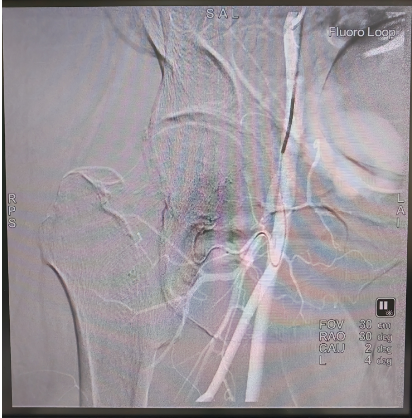

手术在高精度数字减影血管造影机(DSA)的实时引导下,采用局部浸润麻醉,通过穿刺患者大腿根部的股动脉,置入5F血管鞘,将一根5F的造影导管先后插入髂内动脉、髂外动脉内进行血管造影,辨识股骨头的供血动脉,随后将2.7F的微导管分别超选择性的插入到患侧的股骨头供血动脉,并经微导管逐一向病变区域的供血动脉注入溶栓、解痉、扩血管和改善股骨头微循环的药物。手术历经2小时顺利完成,整个手术过程患者处于清醒状态,随时与手术医师交流治疗体验。